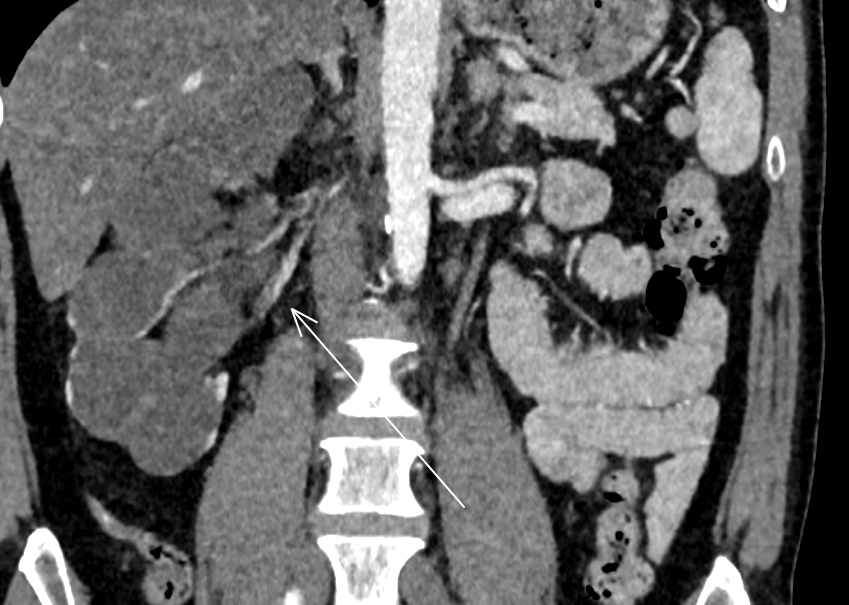

- Sténose à la Jonction Pyélo-Urétérale

- Cause Extrinsèque (Artère Rénale polaire accessoire)